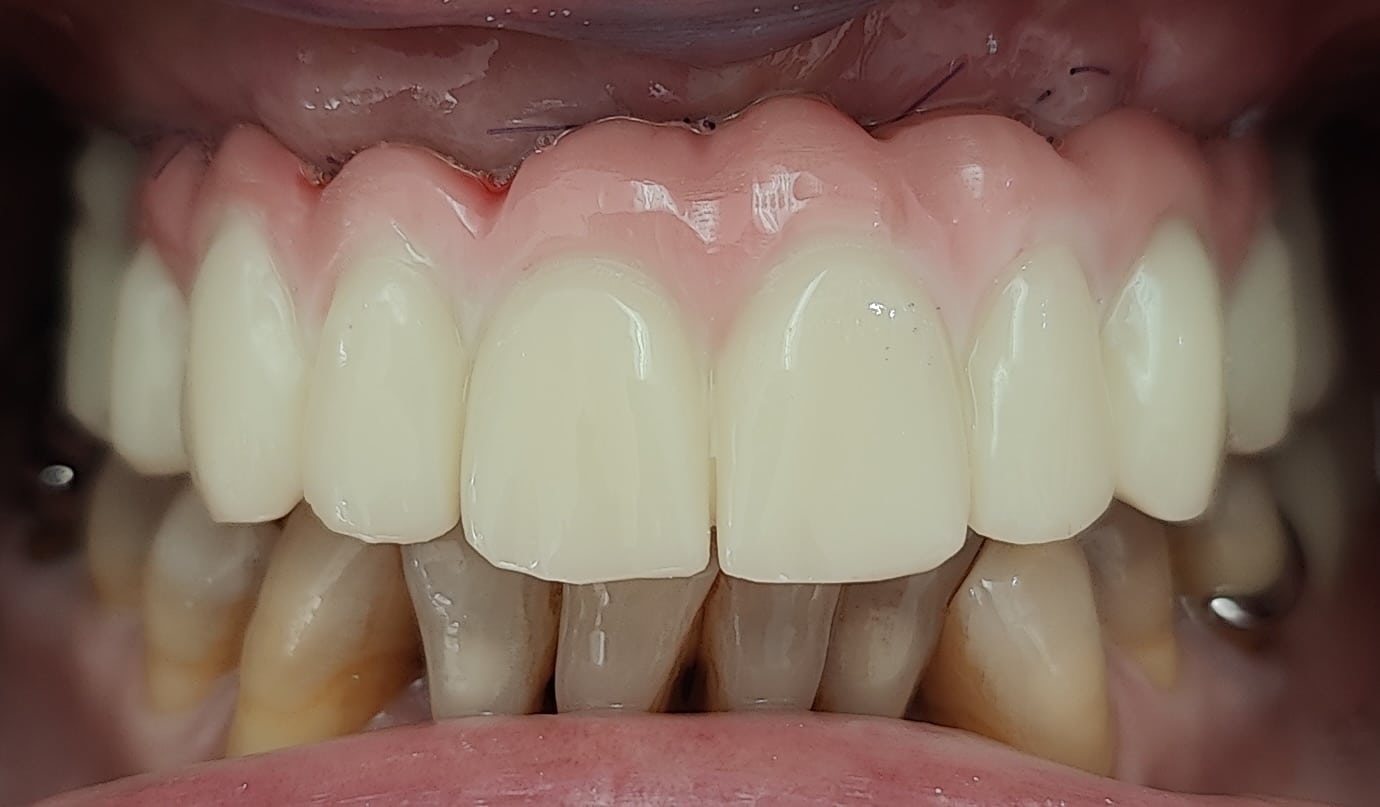

Bridge provisoire en place avec un rendu esthétique satisfaisant :

Détail de la fausse gencive du bridge provisoire en bouche :

Aspects esthétiques à 4 mois :

Pour mémoire cas au départ :

Le point déterminant de la réussite esthétique de cette restauration a tenu au fait qu’au moment de la chirurgie initiale, la ligne de transition implanto-prothétique a été relevée au-delà de la ligne du sourire.